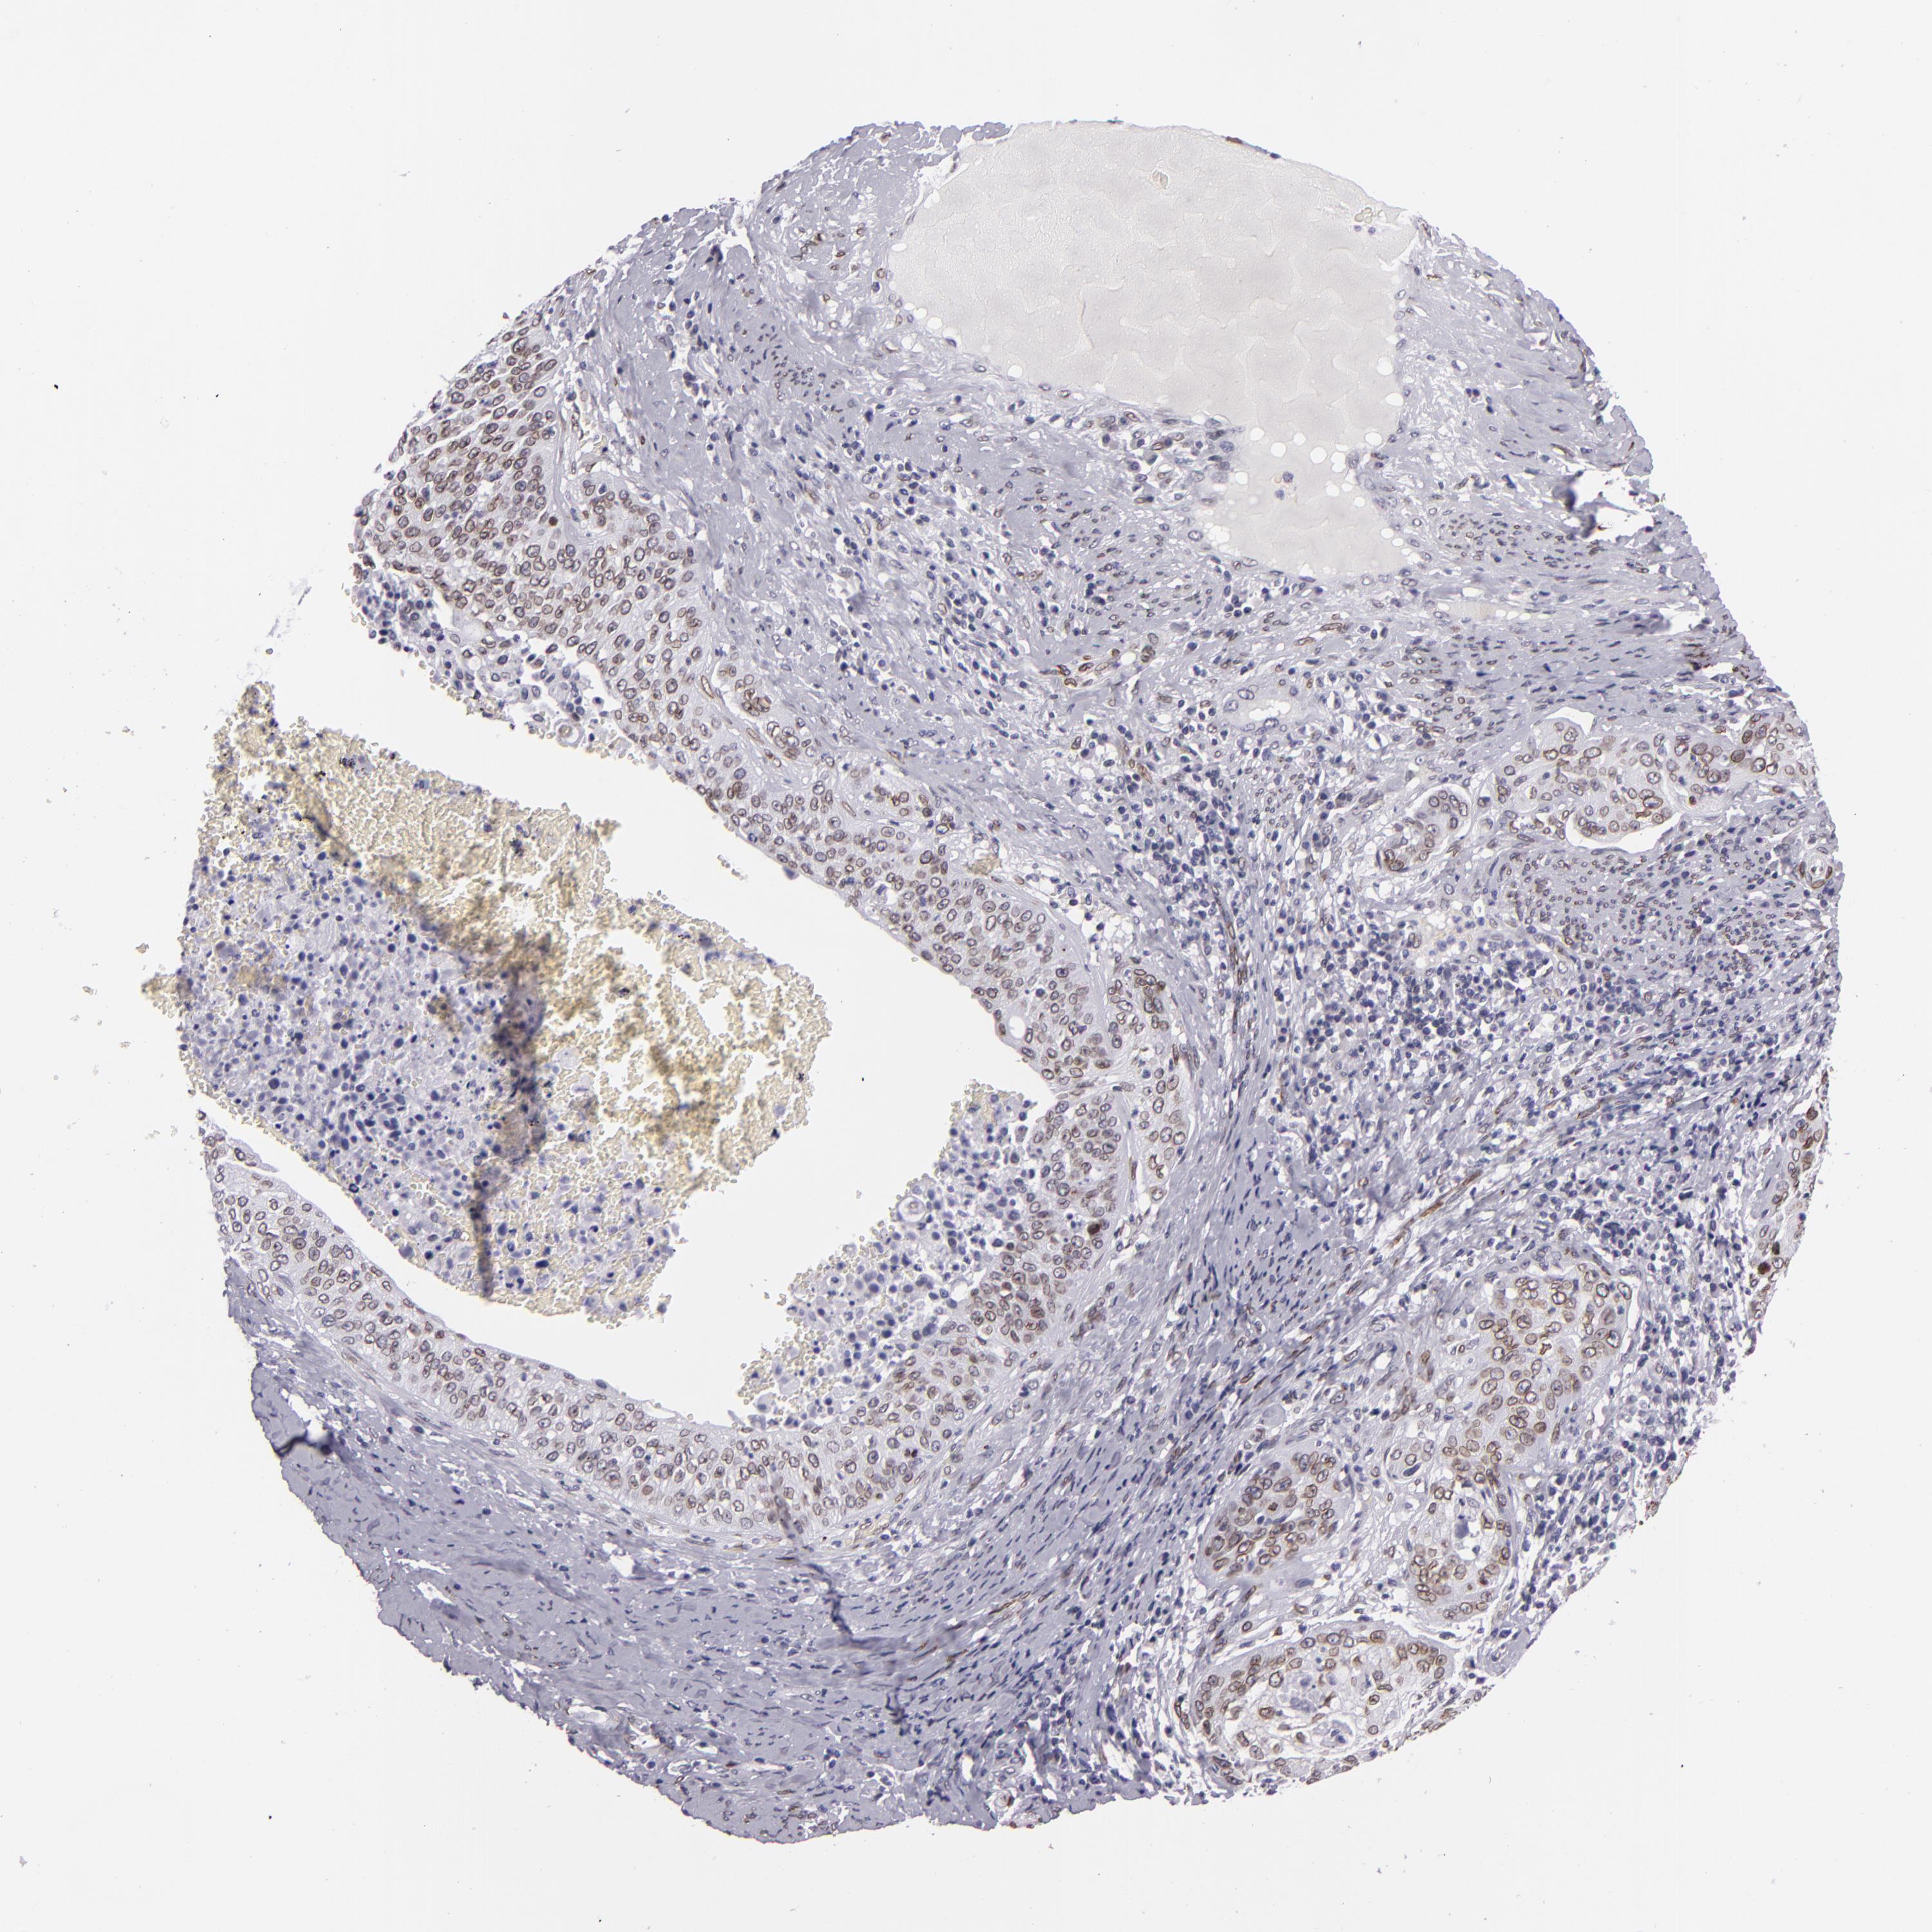

CERVICAL CANCER - Protein expressioni

A mouse-over function shows sample information and annotation data. Click on an image to view it in a full screen mode. Samples can be filtered based on level of antibody staining by selecting one or several of the following categories: high, medium, low and not detected. The assay and annotation is described here.

Note that samples used for immunohistochemistry by the Human Protein Atlas do not correspond to samples in the TCGA dataset.

Antibody stainingi

Antibody staining in the annotated cell types in the current human tissue is reported as not detected, low, medium, or high, based on conventional immunohistochemistry profiling in selected tissues. This score is based on the combination of the staining intensity and fraction of stained cells.

Each image is clickable and will lead to virtual microscopy that enables deeper exploration of all samples and also displays staining intensity scores, fraction scores and subcellular localization as well as patient and tissue information for each sample.

Antibody HPA000609

Antibody CAB001545

Antibody CAB002029

Antibody CAB062552

Squamous cell carcinoma, NOS

Adenocarcinoma, NOS

Adenocarcinoma, Low grade